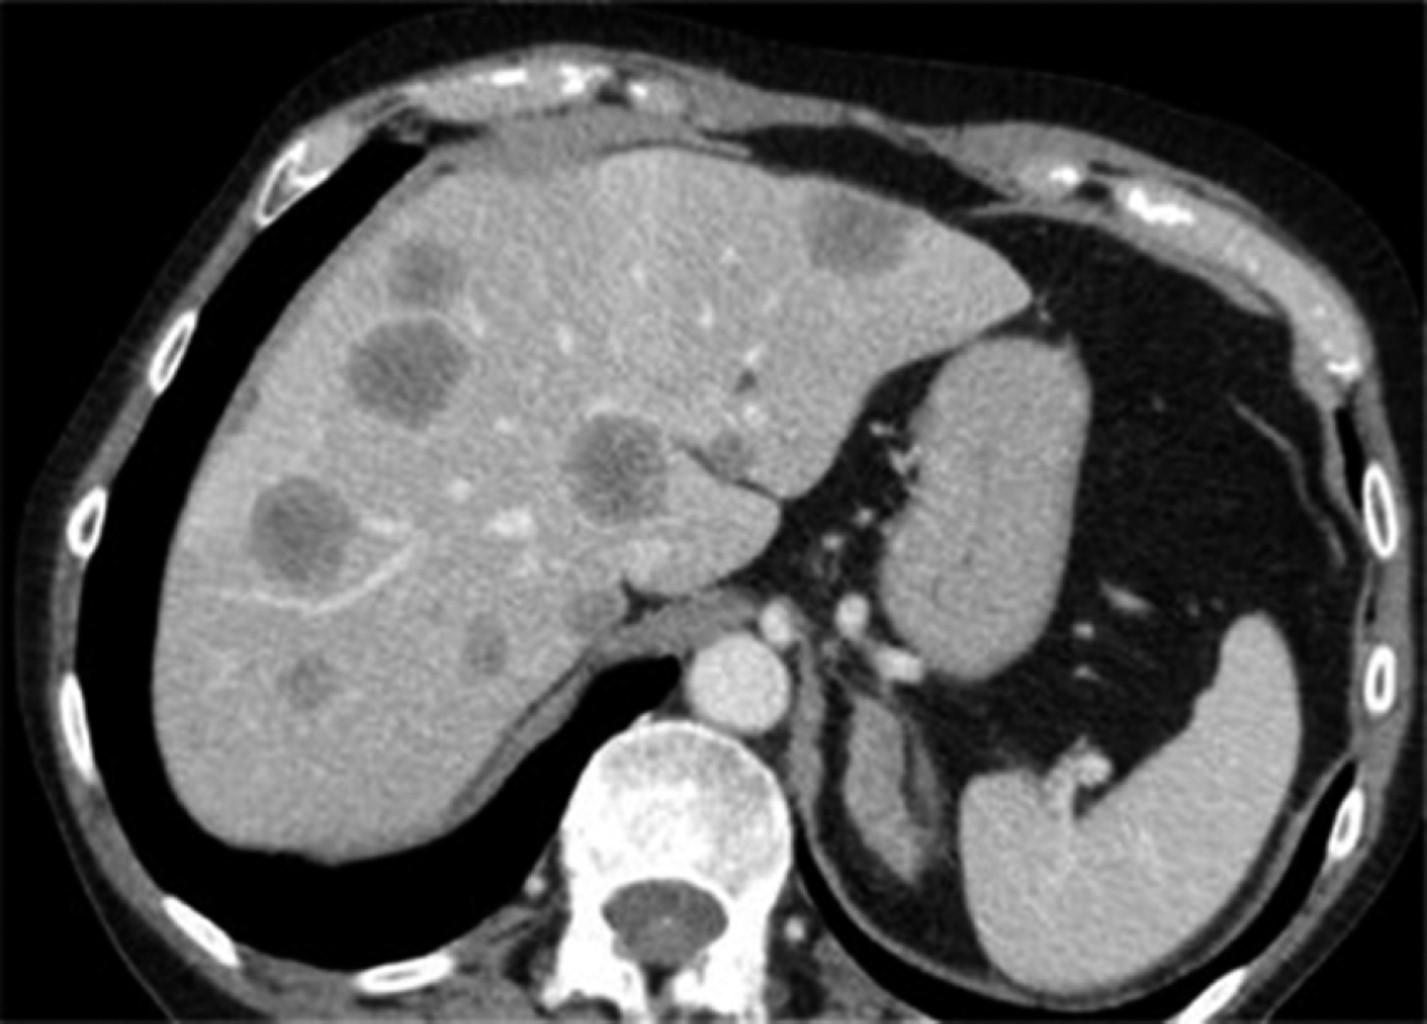

Metachronous hepatic metastatic disease due to colorectal cancer

Colorectal cancer is the third most common malignancy in the world with an incidence of 1.8 million new cases in 2018 and is the second most common cause of cancer death worldwide. Almost 50% of patients will develop liver metastases in the course of their disease. It is very important to know all tools available to treat this type of patients.

Figure 1